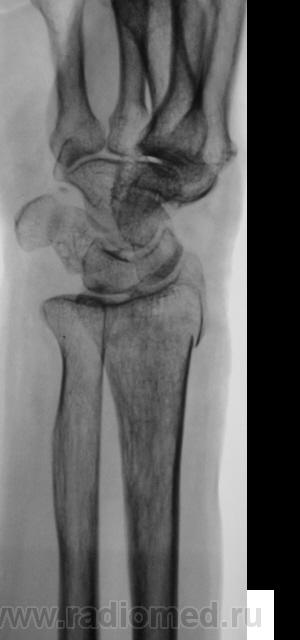

Травма.   Пациент направлен на рентгенографию лучезапястного сустава.

СЛУЧАЙ № 2.